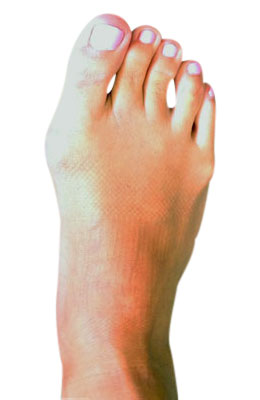

Minimally Invasive Bunion Surgery featuring the miniBunon™ System and Tailors Bunionectomy

Melissa is a 32-year-old businesswoman who could not be off her foot post-surgery, yet she had a severely painful bunion. We performed our miniBunon™ System (our trademarked minimally invasive bunion surgery) and had a dramatic correction with no downtime. Melissa continued to work after her bunion surgery and was back in shoes and full activity at 5 weeks. Melissa could not believe the results of her Bunionectomy resulting in no bony bump, no scar and amazing motion. “After” picture taken immediately following surgery. Note the bunion and bunionette (Tailor’s bunion) in the before picture.